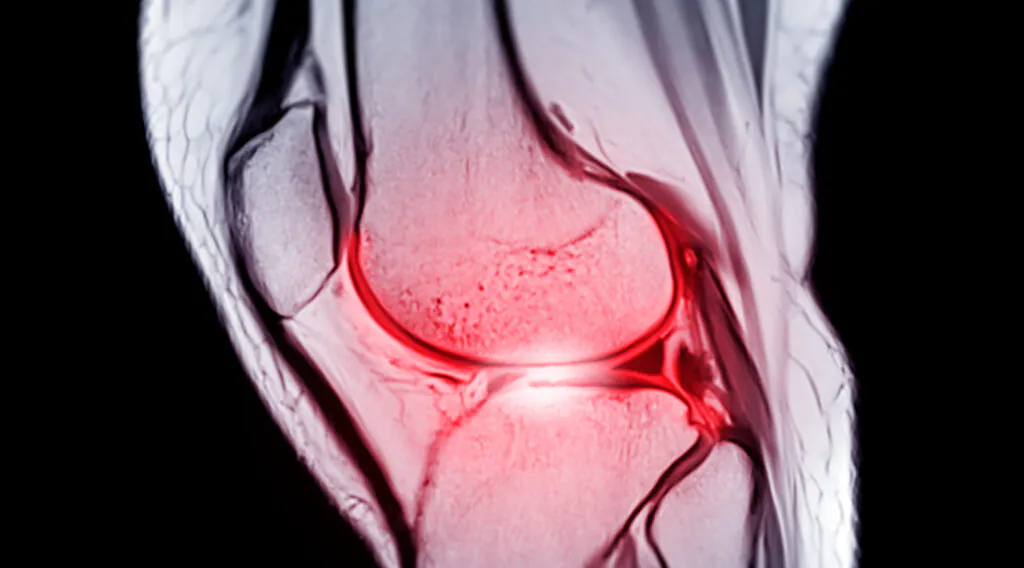

What is an ACL tear?

The ACL (anterior cruciate ligament) is one of the knee’s main stabilizers. It helps control forward movement of the shin and rotational stability—especially during cutting, landing, and deceleration. When the ACL tears, the knee can still move, but it loses a key passive restraint. Strength, coordination, and timing have to do more of the work.

An ACL tear doesn’t automatically mean the knee “gives out” constantly, but it does increase the risk. Swelling, pain, and reflex inhibition can affect muscle output and rotational control becomes more demanding. Fatigue matters more, and in high-speed sports, those limitations show up quickly.